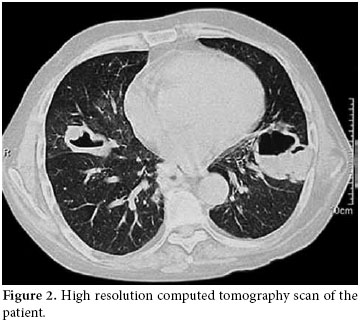

A 50-year-old male patient was admitted to our hospital with symptoms of fatigue, proximal muscle weakness, and bruising. Two years previously, he had manifested symptoms of arthralgia, arthritis, and edema. Because of these complaints, laboratory tests were performed. Nephrotic range proteinuria, a high creatinine level, bicytopenia along with antinuclear antibody (ANA) and Anti-deoxyribonucleic acid (anti-DNA) positivity were determined in these tests. Systemic lupus erythematosus was considered. Type ΙV lupus nephritis was also determined with a kidney biopsy. Endoxan 500 mg pulse and methylprednisolone 1000 mg pulse (3 days) were given to the patient parenterally. After these immunosuppressive treatments, the symptoms of the patient relieved, and corticosteroid treatment was continued as methylprednisolone 1 mg/kg/day at another hospital. The methylprednisolone dosage was not tapered accordingly, and after four months, suffering from fatigue, proximal myopathy, and weakness and the patient was admitted to our clinic. Upon physical examination, no other finding other than proximal muscle weakness was determined. Laboratory findings were white blood cell count: 12300/mm3, hemoglobin: 8.9 g/dl, hematocrit: 24%, MCV: 82 fL, lymphocyte: 200 mm3, platelet: 63000 mm3. Glucose: 79 g/dl, BUN: 109 mg/dl, creatinine: 2.7 mg/dl, uric acid: 8.4 mg/dl, Na: 135 mmol/L, K: 4.6 mmol/L, Cl: 105 mmol/L, Calcium: 8.2 mg/dl, P: 4.0 mg/dl, AST: 12U/L, ALT:39 U/L, LDH: 643 U/L, ALP: 70 U/L, and anti-dsDNA of 1:1280. Total bilirubin: 0.48 mg/dl, direct bilirubin: 0.06 mg/dl, Indirect bilirubin: 0.42 mg/dl, total protein: 5 g/dl, albumin: 2.39 g/dl, Fe: 73 mcg/dl, Iron binding capacity: 212 mcg/dl., PT: 11.1 sn, aPTT: 18.8 sn, INR: 0.90 were found. A chest radiograph taken on admission revealed multiple cavitary lesions (Figure 1). A chest computed tomography (CT) also showed multiple cavitary lesions at the sites of the right medial lobe, right inferior lobe superior segment, and left lingula inferior segment along with nodular lesions at the right inferior lobe superior segment (Figure 2). These lesions were found to be related with intensive and long-term steroid treatment. The cavitary lesions were considered as an opportunistic fungal infection, nocardiosis, or tuberculosis. A smear of sputum was negative for both Gram stain and acid fast bacilli, and cultures related to tuberculosis were found to be negative. A bronchoscopy and endobronchial lavage were performed to determine the etiology of these lesions. No endobronchial lesion was observed. Cultures for tuberculosis, nocardiosis, and fungal infections were taken from bronchoalveolar lavage, and also samples were taken for cytologic examination of lavage. In bronchoalveolar lavage fluid cytology, polymorphonuclear leukocytes was detected, and there were no atypical findings. The sputum specimen was also examined again, and cultures were sterile. The symptoms of the patient had increased progressively. The cavitary lesions had also increased. Because of this progression, high resolution computed tomography (HRCT) was performed. New cavitary lesions were determined at the left pulmonary site in HRCT. Nocardiosis was found positive in bronchoalveolar lavage fluid specimens. The patient was diagnosed as having pulmonary nocardiosis and given intravenous trimethoprim-sulfamethoxazole (320 mg/1600 mg/day), but the patient’s clinical findings worsened. Acute respiratory failure developed on the second day of treatment. Metabolic acidosis and respiratory alkalosis were added to the clinical findings. In arterial blood gas, PH: 7.31, PCO2: 24.8 mmHg, PO2: 35.6 mmHg, HCO3: 12.2 mmol, O2 saturation: 57.9% were found. Oxygen inhalation and anti-obstructive treatment were started. Sepsis and acute respiratory distress syndrome were considered possible , and the patient was sent to the intensive care unit. The patient died one day after being sent to the intensive care unit.

Pulmonary nocardiosis produces an impressive variety of roentgenographic findings, such as segmental infiltrates, lobar infiltrates, small and large cavities, necrotizing bronchopneumonia, necrotizing lobar pneumonia, lobar pneumonia with bulging fissures, small and large abscesses, single or multiple nodules, miliary patterns, masses with central cavitations, pleural effusion, and empyema.[5] Because the radiographic feature of nocardiosis is non-specific and pleomorphic with clinical findings ranging from malaise to respiratory failure, it is difficult to diagnose; therefore, the diagnosis of nocardiosis is often delayed. Multiple nodules and cavitation are more commonly described in acquired immune deficiency syndrome (AIDS) patients.[6,7] Multiple cavitary lesions are very rare in non-HIV patients. In our case, the patient was a man with a diagnosis of SLE, and he had undergone corticosteroid treatment for a long time. Although his test was negative for AIDS, multiple cavitary lesions were seen in his chest X-ray and HRCT. Since the patient was HIV-negative and immunosuppressive, all causes of multiple cavitary lung lesions were investigated. Tuberculosis, fungal infections, and malignancy were considered in the differential diagnosis. Multiple cavitary pulmonary nodules can be easily confused with a variety of other bacterial infections of the lung, including actinomycosis and tuberculosis as well as fungal infections and malignancies. In our patient, all of these causes were eliminated after all of the necessary tests were performed.

As shown in our case, pulmonary nocardiosis can be found in unexpected ways, especially in immunosuppressed patients. This patient showed multiple cavitary lesions on chest X-rays. The association of nocardiosis with SLE has only been rarely determined, and its association with acute respiratory distress syndrome has only been reported in one case.[14] In our case, acute respiratory failure was also found because of nocardiosis, and although treatment for infection was started, the patient died within a few days.

In conclusion, nocardiosis may become a severe infection, and it mainly affects profoundly immunocompromised patients. Differential diagnosis, especially with tuberculosis, often delays the time to a proper diagnosis, which worsens the outcome. New diagnostic tools, such as the polymerase chain reaction, could provide more rapid and reliable results. Nocardiosis should always be considered in the differential diagnosis of indolent pulmonary disease, particularly in the setting of cellular immunocompromise. Pulmonary nocardiosis is expected to be a more frequently-encountered disease due to the increasing use of immunosuppressive therapies. The disease should be considered in the differential diagnosis of multiple cavitary pulmonary nodules on chest radiography, even in HIV-negative immunocompromised patients receiving long-term corticosteroid treatment.